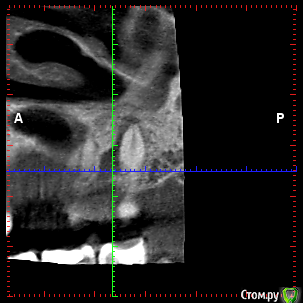

rezo47 Опубликовано 24 сентября, 2015 Автор Поделиться Опубликовано 24 сентября, 2015 Только пришло КТ, вопросов стало больше((( Ссылка на комментарий

kriokov Опубликовано 24 сентября, 2015 Поделиться Опубликовано 24 сентября, 2015 27 удаляйте Ссылка на комментарий

rezo47 Опубликовано 24 сентября, 2015 Автор Поделиться Опубликовано 24 сентября, 2015 (изменено) 27 удаляйтеДиагноз? Изменено 24 сентября, 2015 пользователем rezo47 Ссылка на комментарий

kladoffka Опубликовано 24 сентября, 2015 Поделиться Опубликовано 24 сентября, 2015 Хр пр 2 Ссылка на комментарий

kriokov Опубликовано 24 сентября, 2015 Поделиться Опубликовано 24 сентября, 2015 Диагноз?что хотите, на выбор(например- "не жилец" ) Ссылка на комментарий

red_butler Опубликовано 24 сентября, 2015 Поделиться Опубликовано 24 сентября, 2015 сначала гистология, потом лечение Ссылка на комментарий